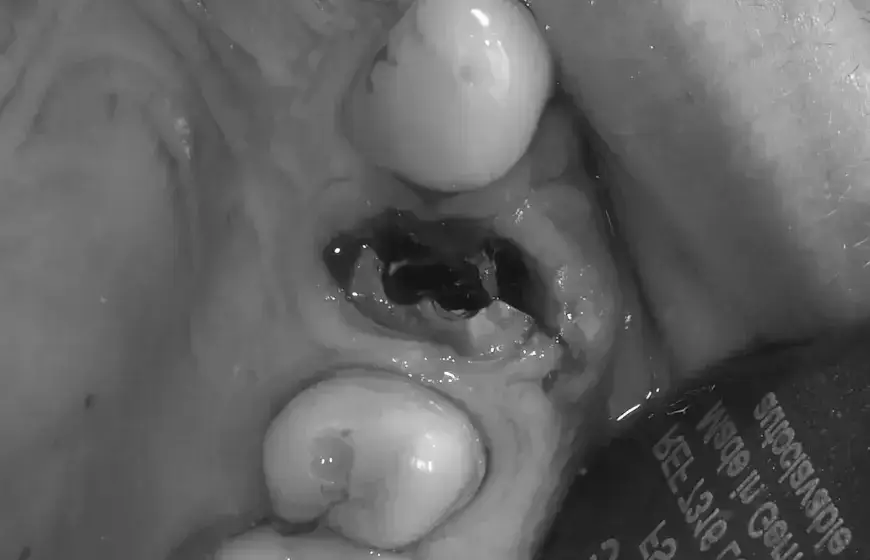

Zaraz po opuszczeniu gabinetu stomatologicznego, Twoim najważniejszym zadaniem jest… nicnierobienie. Wiem, że to może brzmieć dziwnie, ale te pierwsze dwie godziny po ekstrakcji zęba są absolutnie kluczowe dla prawidłowego rozpoczęcia procesu gojenia. To właśnie w tym czasie w zębodole, czyli miejscu po usuniętym zębie, tworzy się niezwykle ważny skrzep krwi. Jego stabilność to podstawa, dlatego tak ważne jest, aby wstrzymać się od jedzenia i picia.Rola skrzepu krwi: twój naturalny opatrunek ochronny

Wyobraź sobie skrzep krwi jako naturalny opatrunek ochronny, który Twoje ciało tworzy w miejscu usuniętego zęba. To nie tylko bariera, która zabezpiecza ranę przed bakteriami i resztkami jedzenia, ale także fundament, na którym będzie budowała się nowa tkanka kostna i dziąsłowa. Bez prawidłowo uformowanego i stabilnego skrzepu, proces gojenia jest znacznie utrudniony, a ryzyko powikłań drastycznie wzrasta. Dlatego tak bardzo zależy mi, abyś o niego dbał od samego początku.

Jeśli zdecydujesz się zjeść lub wypić coś zbyt wcześnie czyli przed upływem wspomnianych dwóch godzin ryzykujesz kilka nieprzyjemnych konsekwencji. Po pierwsze, możesz sprowokować ponowne krwawienie. Po drugie, ruchy żucia i ssania mogą doprowadzić do przemieszczenia lub całkowitego usunięcia skrzepu. To z kolei nie tylko opóźni gojenie, ale także znacząco zwiększy ryzyko wystąpienia suchego zębodołu jednego z najbardziej bolesnych powikłań, o którym opowiem później.

Suchy zębodół to stan, w którym skrzep krwi, który powinien chronić ranę, zostaje utracony lub nie tworzy się prawidłowo. W efekcie, kość zębodołu zostaje odsłonięta na działanie środowiska jamy ustnej, co prowadzi do silnego, pulsującego bólu. Ból ten zazwyczaj pojawia się 2-4 dni po zabiegu i jest znacznie intensywniejszy niż typowy ból pozabiegowy. Może promieniować do ucha, skroni czy szyi, a leki przeciwbólowe często przynoszą jedynie chwilową ulgę. To naprawdę nieprzyjemne doświadczenie, którego każdy chce uniknąć.